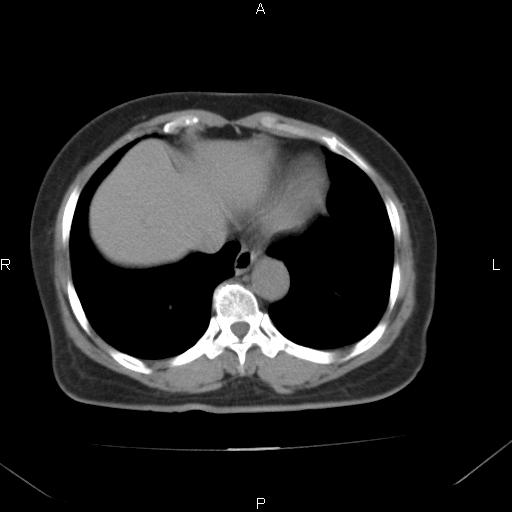

胸腺瘤

女、63Y 双眼睑下垂,早轻晚重。 胸腺瘤???

结果胸腺瘤